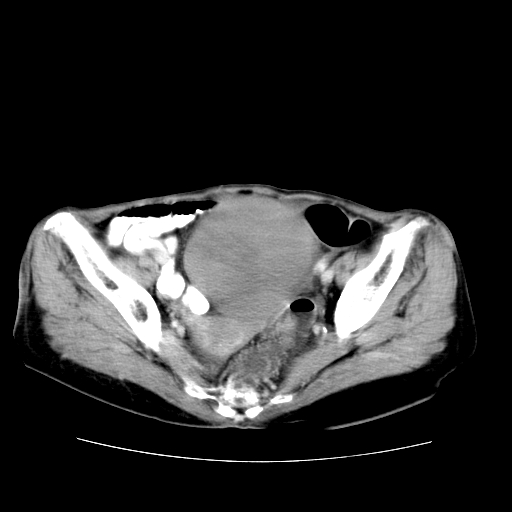

女性,72岁。

主诉下腹部坠痛不适1年余。

子宫增大如孕3月大小,质软,活动可,无压痛。

b超提示:盆腔(子宫前方)低回声团块。

临床诊断:盆腔肿块查。

1、这个肿瘤密度均匀,增强后轻中度均匀性强化,与左侧附件关系密切,肿瘤边缘光整、清晰。

2、左侧卵巢增大呈8×8×10cm大小,实性,表面光滑,边清,左侧输卵管爬行于左卵巢上,子宫萎缩。右输卵管、卵巢萎缩。

3、病理号:092658

左侧卵巢纤维瘤(性索间质肿瘤)

卵巢纤维瘤为良性卵巢性索间质肿瘤,常为单侧发病,当合并腹水或胸腹水时称麦格斯(meigs)综合征,肿瘤切除后胸腹水可消失。ct表现为盆腔内边界清楚的圆形或椭圆形肿块,常有分叶或不规则;肿瘤多为实性,少数为囊性、囊实性,完全囊性者可见壁结节。实性部分与子宫等密度;增强扫描常为轻度强化或几乎不强化。